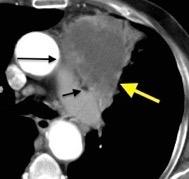

Diafragma “colgante” (“dangling sign”)

(“Dangling sign”)

TC. Mejor con multicorte. (reconstrucciones).

Asociación: Aire en pared.

Fracturas costal .Rotura esplénica. Neumoperitoneo.

Diafragma discontinúo Herniación de la grasa omental

Desser TS et al.The dangling diaphragm sign: sensitivity and comparison with existing CT signs of blunt traumatic diaphragmatic rupture. Emerg Radiol 2010